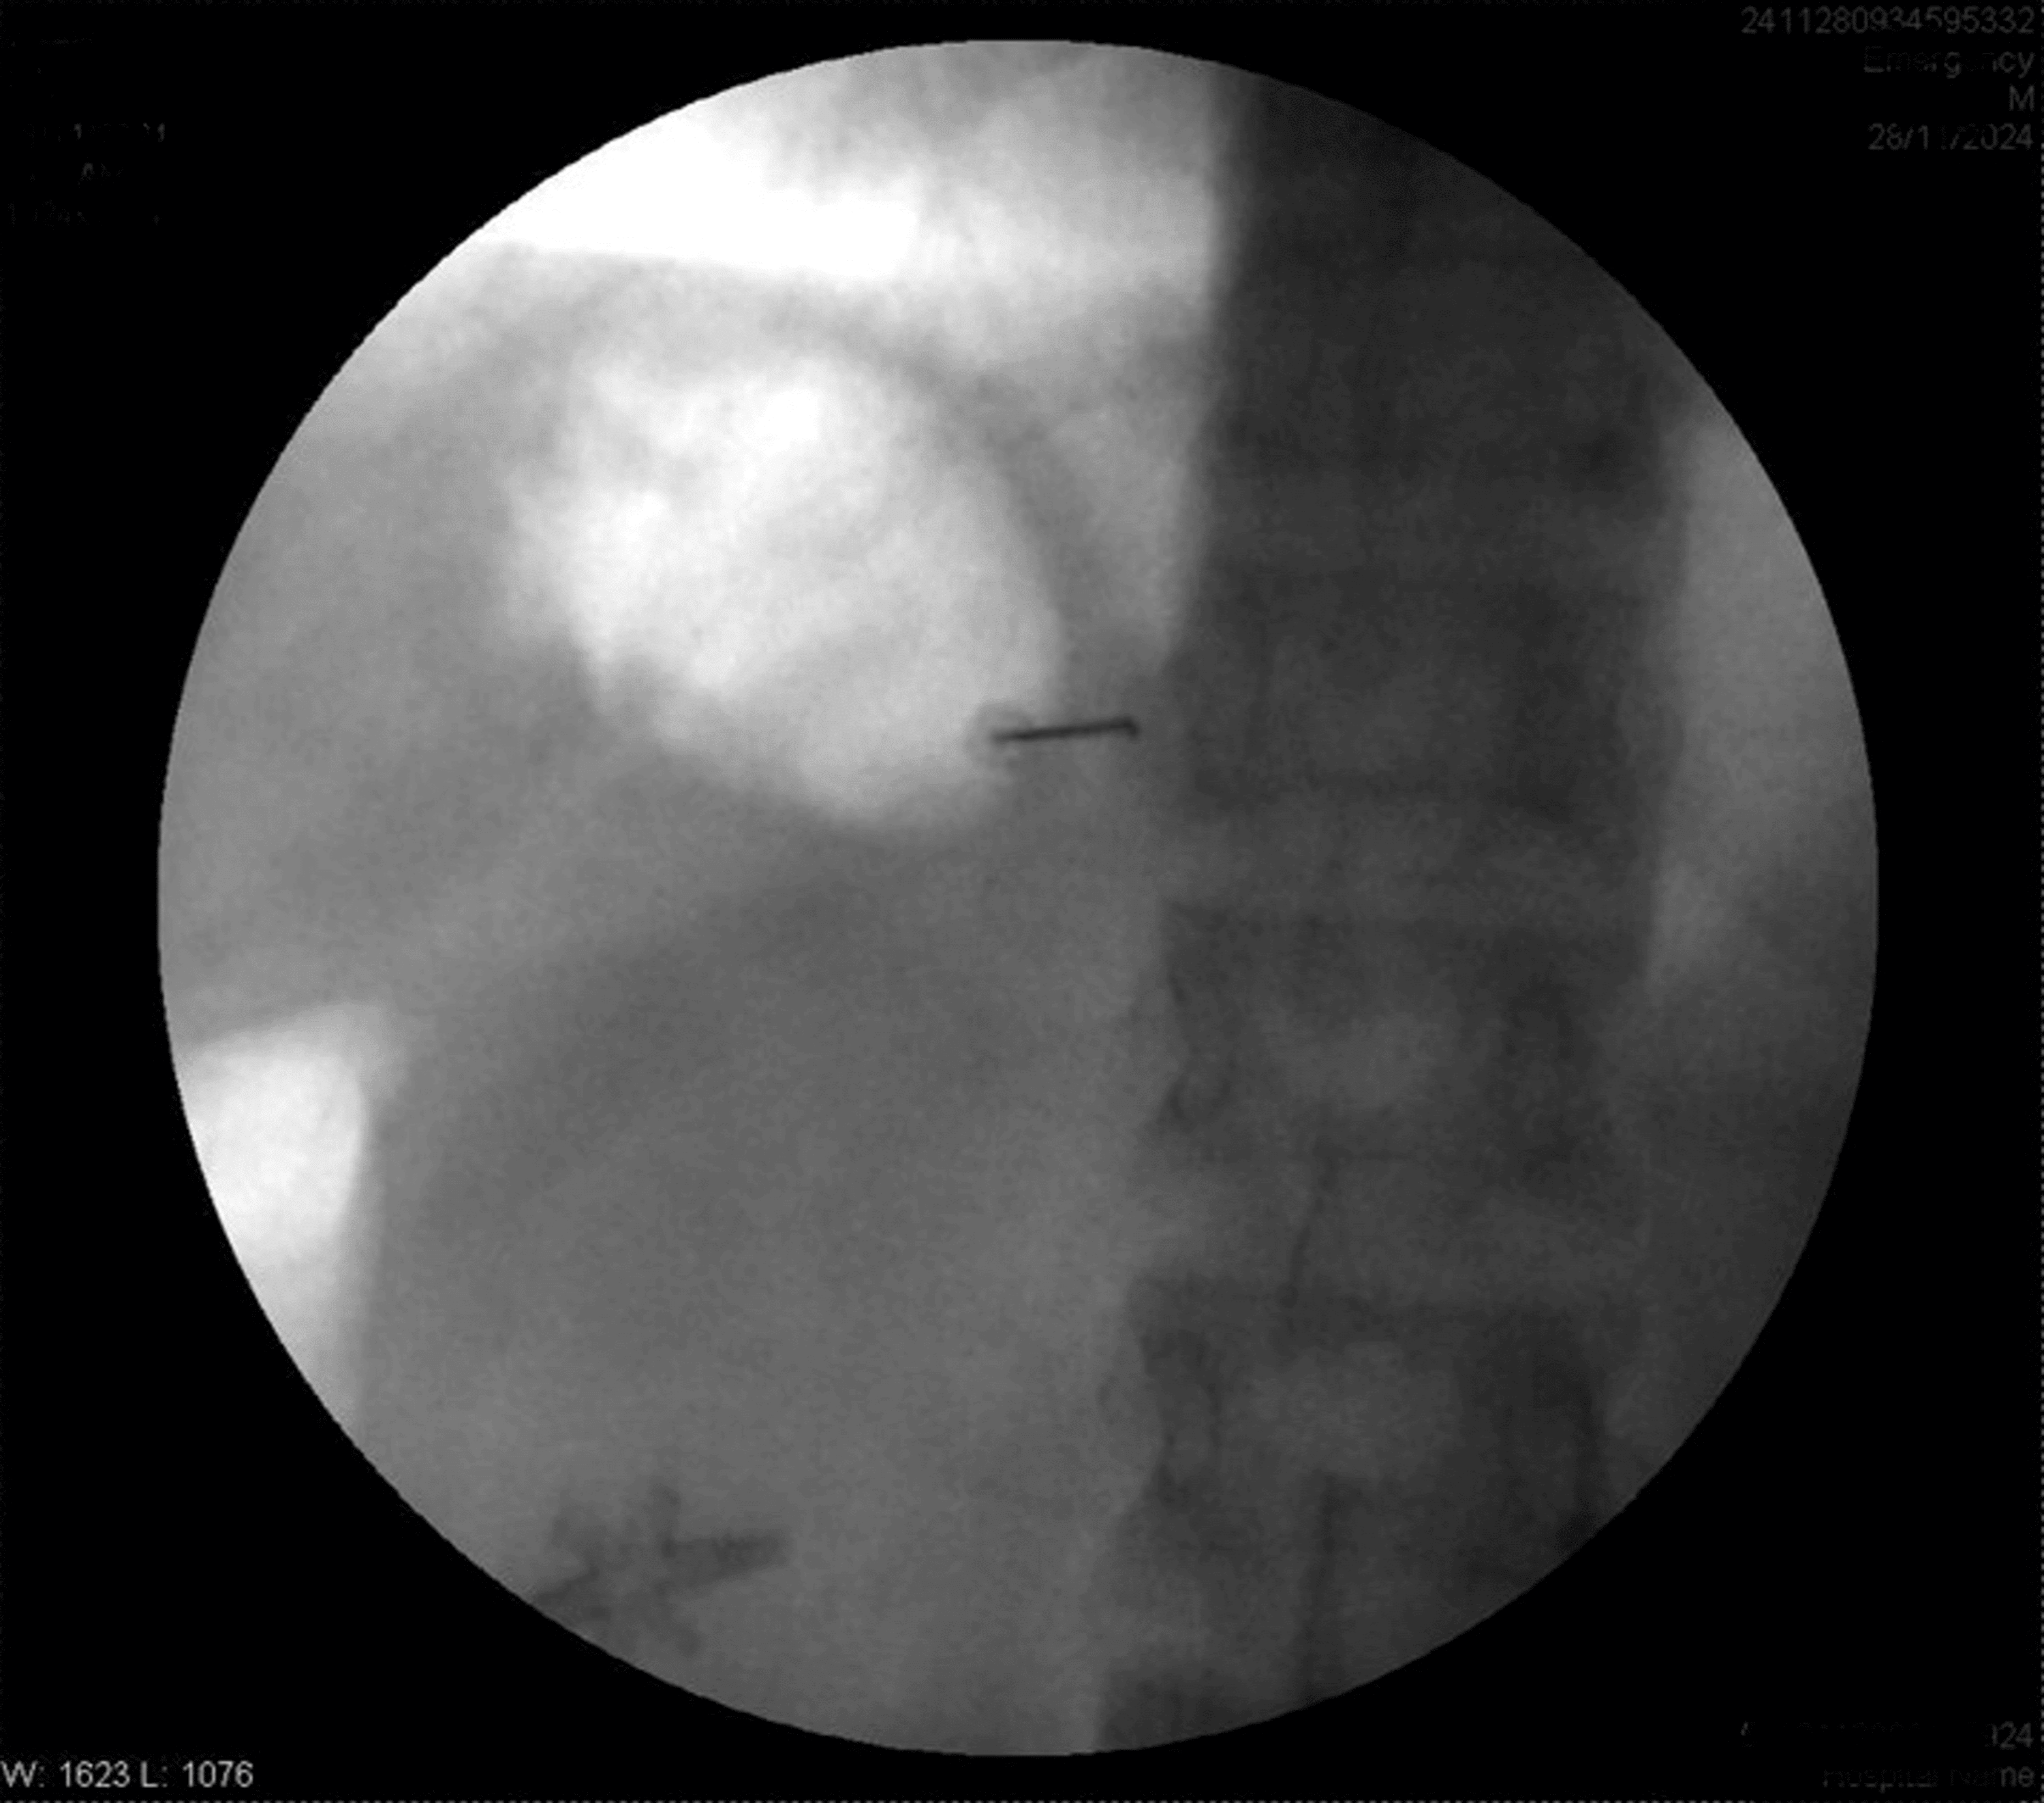

The patient was positioned prone. After painting and draping, the transverse process of T8 was located on the right side with the help of a C-arm. A Quincke needle (22 G) was inserted under fluoroscopic guidance to reach the transverse process of T8. The needle tip was advanced caudally along the transverse process until a loss of resistance was felt. The needle’s position was confirmed via fluoroscopy by injecting iohexol 300 radiocontrast dye, with images obtained in both anteroposterior and lateral views (Figures 1–4).